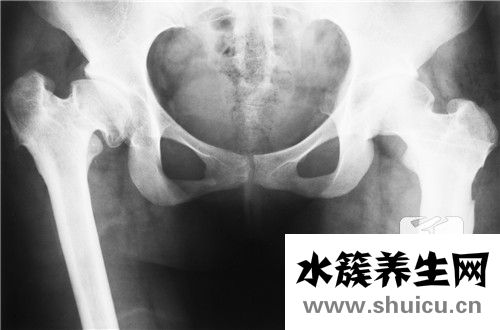

骨盆在醫學上被稱為板骨,因為骨盆看起來像一個盆,所以當嬰兒還在媽媽肚子里的時候,骨盆就是他們的窩床。所以在老一輩人的意識里,認為盆骨大的女人容易養是不無道理的。但是因為骨盆橫跨整個腰部,有些...